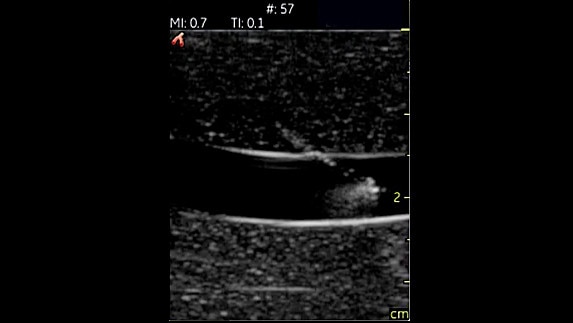

Yumuşak Doku